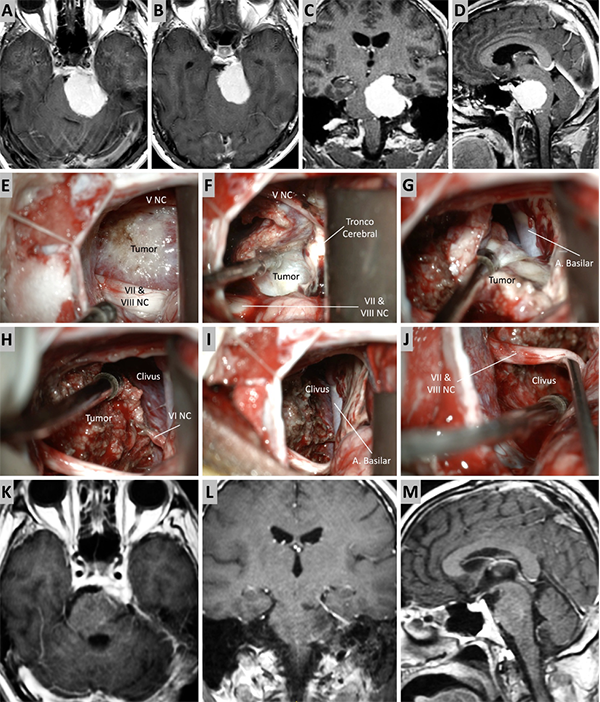

Figura 4. Caso ilustrativo #2. MRPC con implantación petroclival, extensión a la fosa media y compromiso de la incisura tentorial. Paciente con audición conservada. A. Corte axial sobre la región clival media. B. Corte axial sobre la región clival superior. Corte Coronal. D. Corte sagital donde se observa el efecto compresivo sobre el tallo cerebral. E-J. Se realizo un abordaje retrosigmoideo. K-N. Se muestra las imágenes en distintos cortes con resección quirúrgica completa.